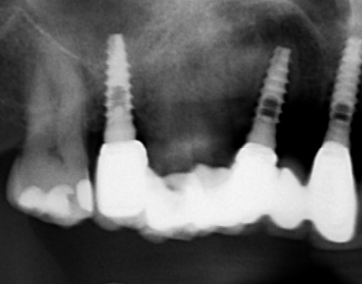

Paciente acude a consulta con implante en posición del 35, colocado hace 9 años en una clínica que ha cerrado. No lleva pilar de cicatrización. Si me pudieseis ayudar a [...]